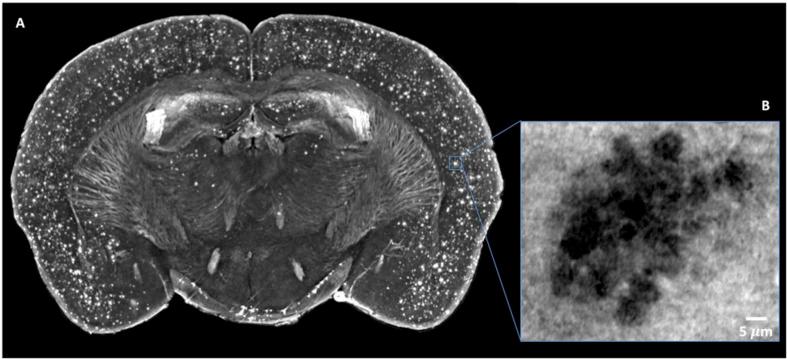

We report a qualitative study on central nervous system (CNS) damage that demonstrates the ability of X-ray phase contrast tomography (XPCT) to confirm data obtained with standard 2D methodology and permits the description of additional features that are not detected with 2D or other 3D techniques. In contrast to magnetic resonance or computed tomography, XPCT makes possible the high-resolution 3D imaging of soft tissues classically considered "invisible" to X-rays without the use of additional contrast agents, or without the need for intense processing of the tissue required by 2D techniques. Most importantly for studies of CNS diseases, XPCT enables a concomitant multi-scale 3D biomedical imaging of neuronal and vascular networks ranging from cells through to the CNS as a whole. In the last years, we have used XPCT to investigate neurodegenerative diseases, such as Alzheimer's disease (AD) and multiple sclerosis (MS), to shed light on brain damage and extend the observations obtained with standard techniques. Here, we show the cutting-edge ability of XPCT to highlight in 3D, concomitantly, vascular occlusions and damages, close associations between plaques and damaged vessels, as well as dramatic changes induced at neuropathological level by treatment in AD mice. We corroborate data on the well-known blood-brain barrier dysfunction in the animal model of MS, experimental autoimmune encephalomyelitis, and further show its extent throughout the CNS axis and at the level of the single vessel/capillary.

我们报告了一项关于中枢神经系统(CNS)损伤的定性研究,该研究证明了X射线相衬断层扫描(XPCT)能够证实通过标准二维方法获得的数据,并允许描述二维或其他三维技术未检测到的其他特征。与磁共振或计算机断层扫描不同,XPCT无需使用额外的造影剂,也无需对二维技术所需的组织进行高强度处理,就能对传统上被认为对X射线“不可见”的软组织进行高分辨率三维成像。对于中枢神经系统疾病的研究而言最重要的是,XPCT能够对从细胞到整个中枢神经系统的神经元和血管网络进行多尺度三维生物医学成像。在过去几年中,我们使用XPCT来研究神经退行性疾病,如阿尔茨海默病(AD)和多发性硬化症(MS),以阐明脑损伤并扩展通过标准技术获得的观察结果。在这里,我们展示了XPCT的前沿能力,可以在三维空间中同时突出显示血管闭塞和损伤、斑块与受损血管之间的紧密关联,以及AD小鼠经治疗后在神经病理学水平上引起的显著变化。我们证实了多发性硬化症动物模型实验性自身免疫性脑脊髓炎中众所周知的血脑屏障功能障碍的数据,并进一步展示了其在整个中枢神经系统轴以及单个血管/毛细血管水平上的范围。